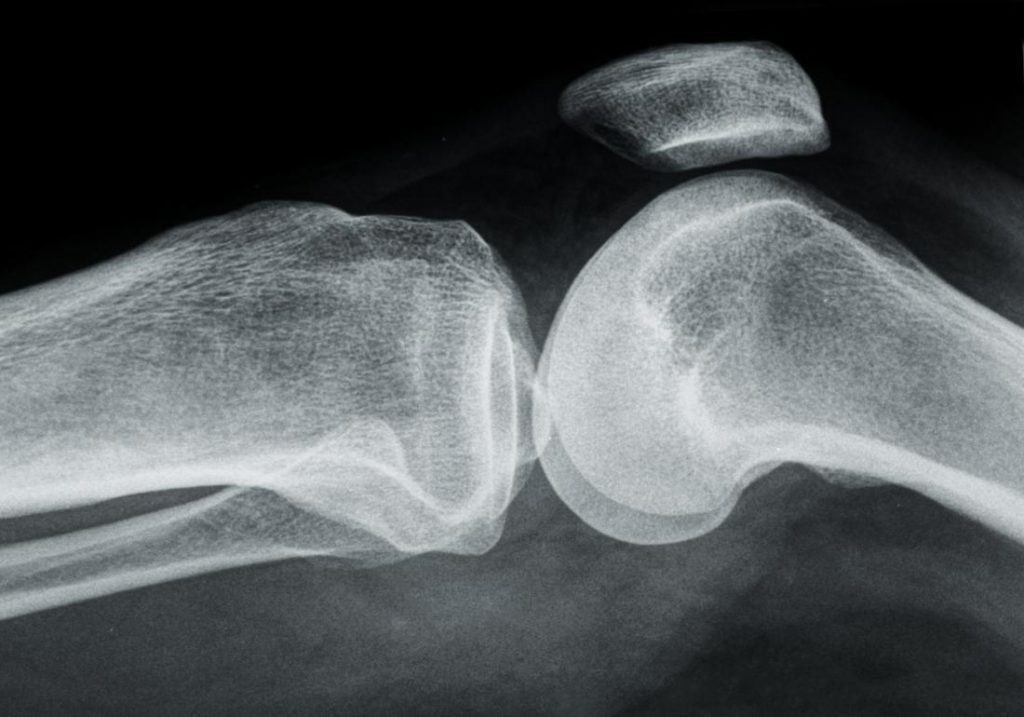

Viêm xương khớp được chẩn đoán như thế nào?

Khi chẩn đoán, bác sĩ sẽ kiểm tra phần dịch xung quanh các khớp bị viêm bằng một trong các xét nghiệm sau:

Sử dụng tia phóng xạ tần số thấp để nhìn rõ xương: X-Quang cho thấy sự mất sụn, tổn thương xương và lồi xương. X-Quang có thể không chỉ ra được tổn thương viêm khớp sớm nhưng chúng có thể được dùng để theo dõi tiến triển của bệnh;

X-Quang cho thấy sự mất sụn, tổn thương xương